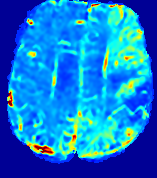

Slice #1Slice #2Slice #3Slice #4Slice #5Slice #6Dgtsuperscript𝐷gtD^{\text{gt}}Refer to captionRefer to captionRefer to captionRefer to captionRefer to captionRefer to caption(a)Refer to captionRefer to captionRefer to captionRefer to captionRefer to captionRefer to caption(b)Refer to captionRefer to captionRefer to captionRefer to captionRefer to captionRefer to caption(c)Refer to captionRefer to captionRefer to captionRefer to captionRefer to captionRefer to caption(d)Refer to captionRefer to captionRefer to captionRefer to captionRefer to captionRefer to caption(e)Refer to captionRefer to captionRefer to captionRefer to captionRefer to captionRefer to caption(f)Refer to captionRefer to captionRefer to captionRefer to captionRefer to captionRefer to captionRefer to caption000.060.060.060.120.120.120.180.180.180.240.240.240.300.300.30(mm2/s)𝑚superscript𝑚2𝑠(mm^{2}/s)

Figure 13: PIANO effectiveness and robustness testing: diffusion imaging via diffusion. Top row shows Dgtsuperscript𝐷gtD^{\text{gt}} used for simulating the ground truth pure diffusion. (a)-(f) refer to the results for D𝐷D estimated from the ground truth pure diffusion image time-series where Rician noise at levels 0%, 2%, 4%, 6%, 8%, 10% was added respectively.

Note this is likely not a spatially representative ground-truth for perfusion imaging, as it measures different effects from diffusion imaging. However, we still use it as a quasi-realistic pattern of diffusivity in the brain. We also added 2%, 4%, 6%, 8%, 10% levels of Rician noise to obtain simulations of ‘Diffusion Imaging’. The estimated Destsuperscript𝐷estD^{\text{est}} given concentrations of all noise levels for one patient are shown in Fig. 13, PIANO estimation results for all patients are summarized in Fig. 11 (b). Again, PIANO demonstrates its capability to recover the underlying diffusion field. In Fig. 13, when the noise level is increasing, some noisy patterns indeed appear in the associated Destsuperscript𝐷estD^{\text{est}}. Note that the ground truth diffusivity applied in this simulation experiment is about ten times larger than the diffusivity estimated in reality (Fig. 3, Fig. 4).